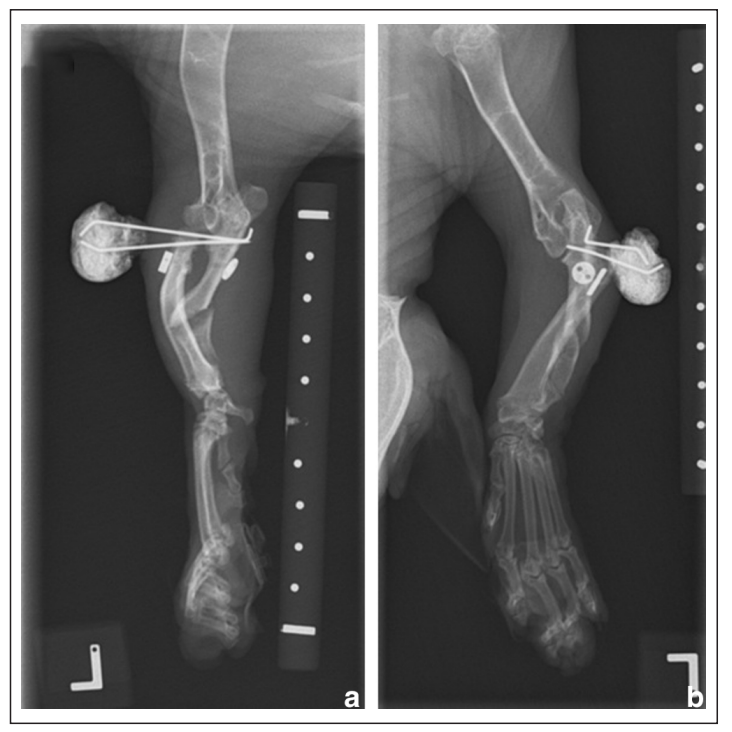

术后3周,精神良好、警觉且反应灵敏,未报告并发症。左前肢跛行评分为3/10,触诊或肘关节的屈伸时无疼痛,但肘关节活动范围有轻度减少。X光片显示桡骨头有轻度持续性半脱位,尺骨截骨处有重塑的迹象,但未见明显的骨痂形成(下图)。

↑ 左前肢术后3周的 (a) 正侧位和 (b) 头尾位X光片。与术后即刻X光片相比,植入物位置未变。桡骨头仍存在半脱位,尺骨截骨处显示出一些重塑迹象。

在两根发散的桡尺骨克氏针上方进行了皮肤切开,并顺利将其移除。术后拍摄了X光片以记录植入物的移除(下图)。给予美洛昔康(0.05 mg/kg,PO,q24h)14天和加巴喷丁(15 mg/kg,PO,q8h)4周。

↑ (a) 左前肢移除临时克氏针3周后的正侧位和 (b) 头尾位X光片。桡骨头显示出一定程度的半脱位,主观上与移除克氏针前的状态相似。